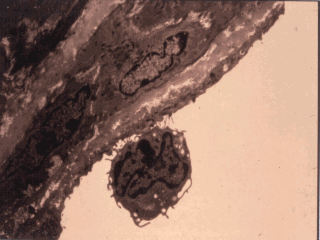

What might acute phase cytokines do? This slide shows an effect of cytokine activation of endothelial cells. These cells on stimulation with TNF-alpha, IL-1, IL-6 expressed number of adhesion molecules causing rolling and the adherence of lymphocytes which may will be the earliest phases of the formation of fatty streaks in the atherosclerotic plague.